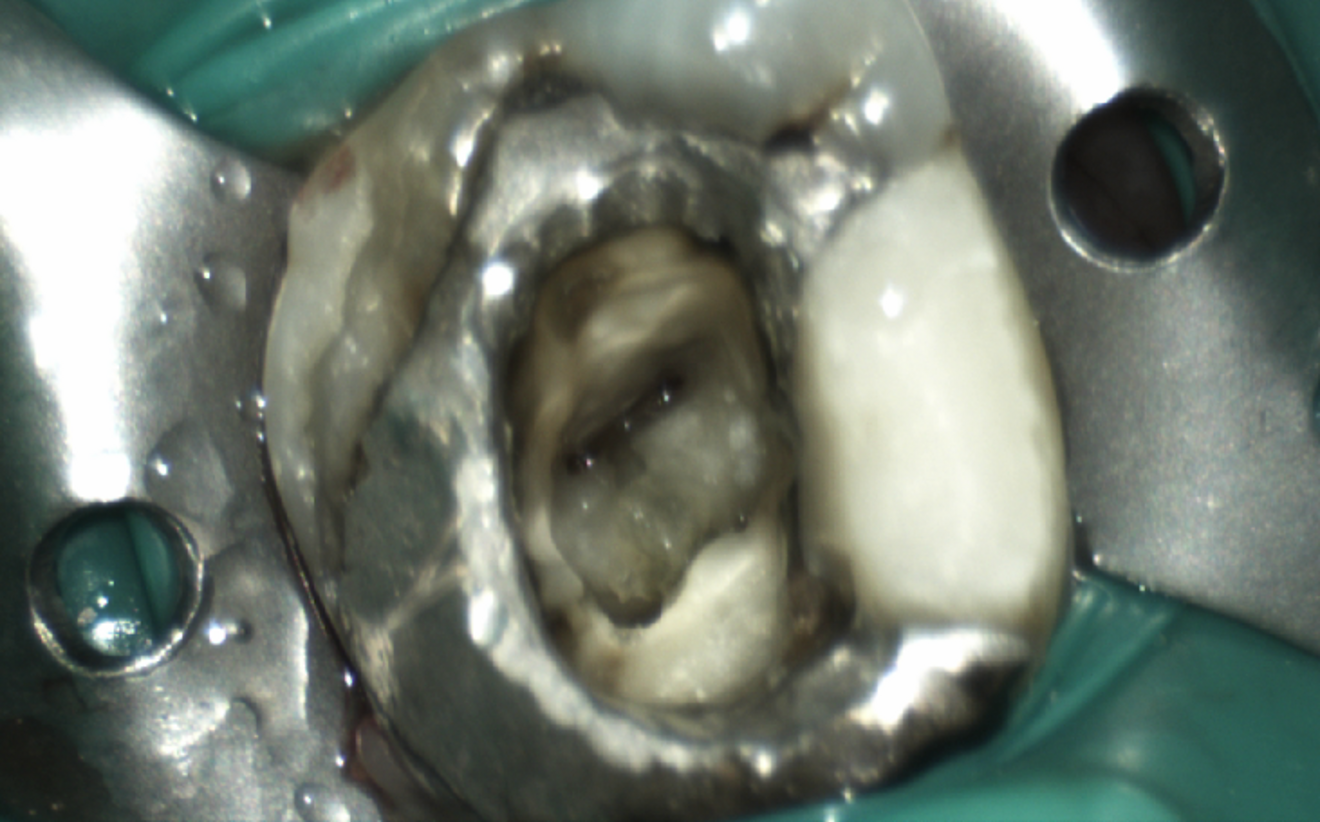

Fig. 4: Post-op radiograph showing the temporary filling.